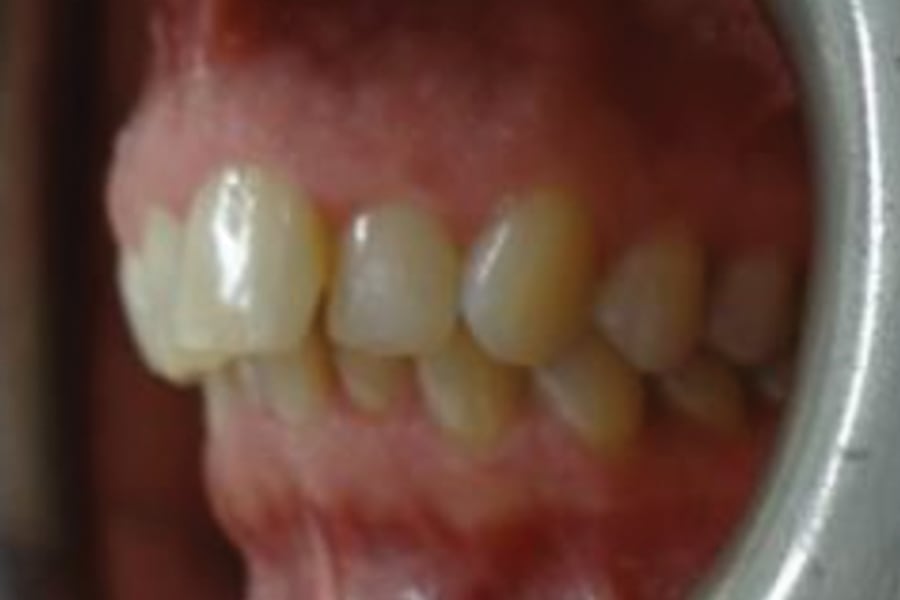

A 54-year-old woman presented with a chief complaint of teeth crowding. After comprehensive digital records were obtained, ClearCorrect® aligner therapy (Straumann, clearcorrect.com) was chosen with an anticipated 12-month treatment duration. The patient exhibited moderate anterior crowding, a class II molar relationship, and narrow arches. The treatment plan aimed to resolve the class II discrepancy, expand the arches, and establish proper anterior alignment. A total of 25 active aligners plus two retention aligners were prescribed. Attachments were selectively placed on the maxillary and mandibular canines to premolars, minimizing bulk while maintaining control over torque and posterior alignment. The patient was instructed to wear class II elastics full-time, which was crucial to achieving molar correction and arch expansion. Her outstanding compliance with class II elastics contributed to a significant improvement in molar position and transverse arch development. After completing the active phase, the patient transitioned to retainers to ensure long-term stability of the results. Given the patient’s initial class II occlusion, monitoring retention was emphasized to prevent relapse. The patient was extremely pleased with the outcome, demonstrating a broadened smile and improved occlusal function. This case underscores the effectiveness of ClearCorrect’s aligners in adult patients, particularly when combined with compliant elastic wear and targeted expansion strategies.